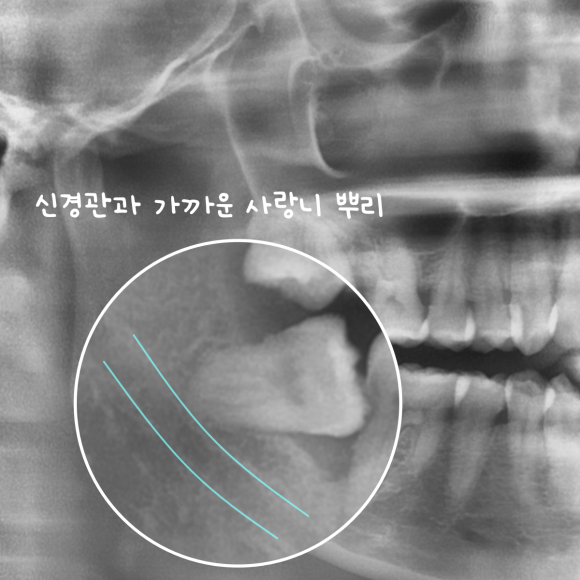

화곡역사랑니

촬영일 : 240610

이번 케이스에서도 오른쪽 아래 사랑니는

뿌리가 신경관을 따라 휘어 들어간 형태였지만

신경의 깊이와 방향을 미리 파악하고

각도와 분할 순서를 세밀하게 계획했습니다.

분할 발치 과정

치관(윗부분)과 치근(뿌리)을 나누어 한 번에 힘을 주지 않고

작은 단위로 분할 제거하기로 했는데요.

이렇게 하면 신경 손상을 피하면서 통증과 회복 부담을 줄일 수 있습니다.